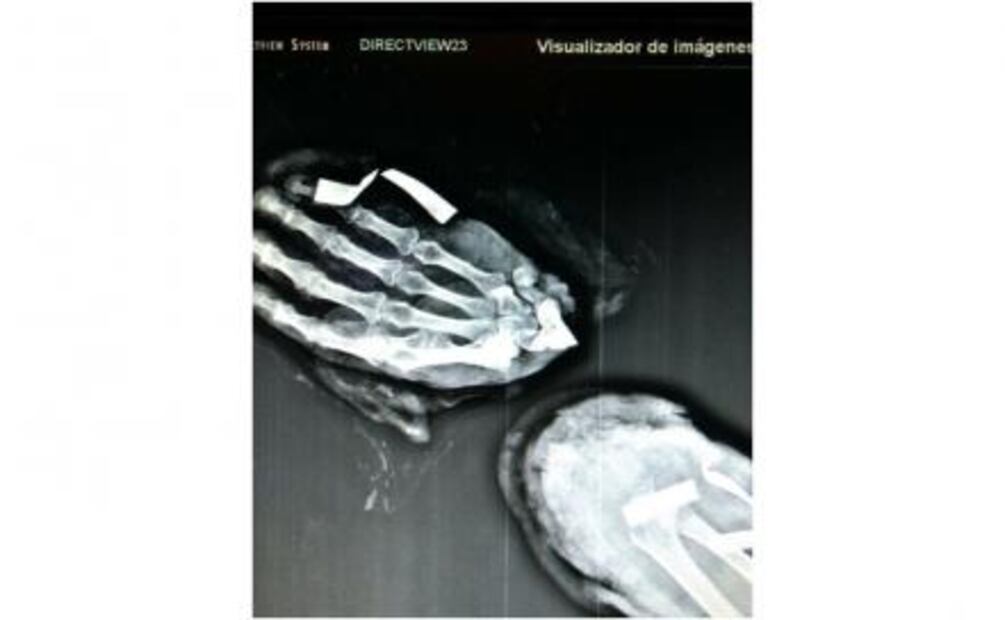

“El caso de este paciente es una carpectomia de la primera fila del carpo y se hace una fusión con el resto del radio; se centraliza la mano para una forma anatómica y se fija con un apartado ortopédico, que es un fijador externo. Se usaron clavillos de fijación y probablemente sea suficiente para que haga una artrodesis, que es una fusión de la muñeca”, indicó.

Y agregó: “La complejidad es que es un procedimiento de microcirugía y de reconstrucción de una extremidad, entonces hay que ir poco a poco; localizar los vasos sanguíneos primero, perneabilizarlos y hacerle la anastomosis, que médicamente es el término que usamos para conectar los vasos sanguíneos. El término medico es un reimplante de mano que se hace con una técnica de microcirugía”.

Al médico José Aguilar Romero lo contactó un familiar del catedrático, Ramón Figueroa Cantoral, y de inmediato se trasladó de Pichucalco, Chiapas, en donde se encontraba hasta la ciudad de Villahermosa, y junto con el cirujano Héctor Palomino, quien es el jefe de traumatología del Hospital de alta especialidad, Gustavo Antonio Rovirosa, estuvieron al frente del reimplante de mano, el cual es la primera que se realiza en el estado y el cuarto en el país. Antes ya se había logrado una en Monterrey, Nuevo León y dos en la Ciudad de México. El costo aproximado es de 500 mil pesos.